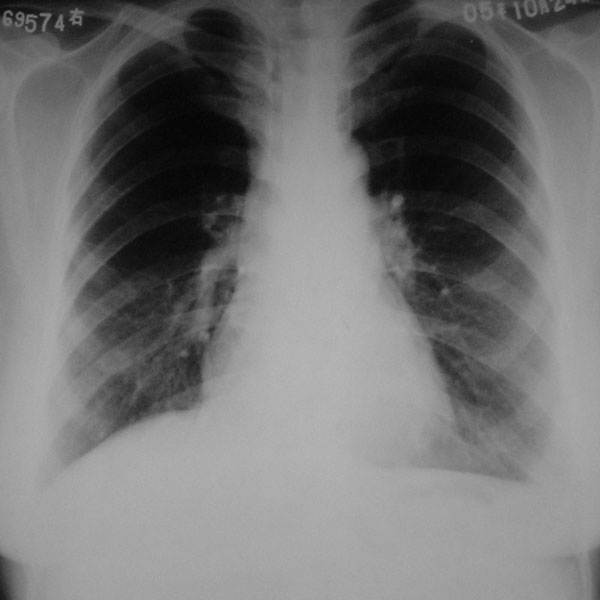

再来个空洞性肺癌,男,58岁,有咳嗽,咳痰,咯血,我看到片子时已经是治疗后复查了,第一次片子,空洞里充满了积液。

[本贴已被 jiajie 于 2006-3-8 19:19:06 修改过]